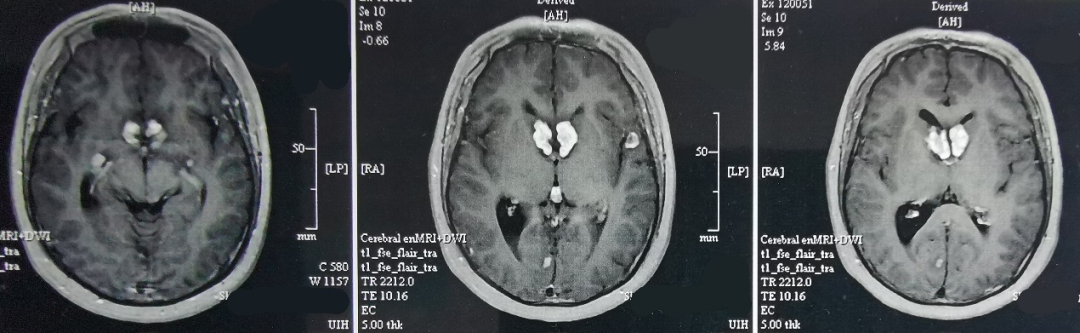

2020年5月,MRI提示病灶增大,尤其是左颞内侧病灶更为明显(图3)。进一步PET-CT检查,提示颅内多发局灶FDG代谢异常升高(片子遗失)。

图3、第2次手术前头颅MR增强影像。